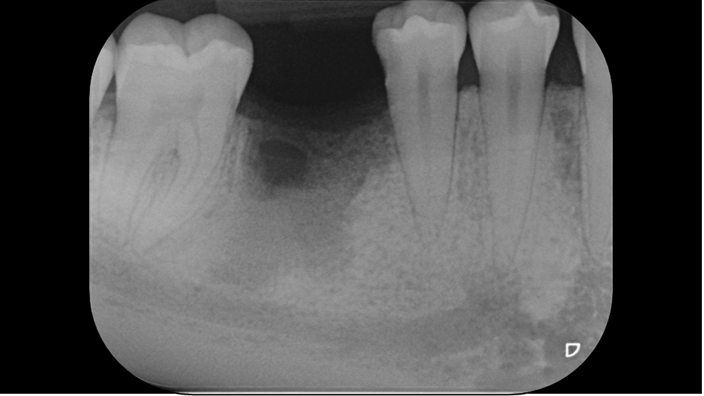

Clinical case: # 46 implant placement & GBR using i-Gen membrane for significant vertical resorption & mixed bone defect

- Courtesy of Dr. Iulian Filipov, Romania -

AnyRidge, mandibular posterior, i-Gen, resorption, bone defect, bone regeneration, space management, #46, GBR, Dr. Iulian Filipov